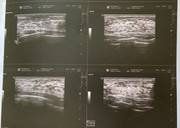

dottore le riporto il referto, in quanto avvertivo un fastidio come una “presenza dura” e dolorosa nel QII del seno sinistro

L'esame ecotomografico delle regioni mammarie, eseguito con sonda ad elevata frequenza da 12 Mhz e 18 Mhz risoluzione, mediante scansioni radiali lungo il decorso dei dotti galattofori ha visualizzato bilateralmente un regolare profilo dermo-epidermico.

Normo-rappresentati gli strati adiposi sottocutanei e retroghiandolari.

I corpus mammae presentano ecostruttura omogenea, iperecogena, come da seno denso giovanile in assenza di immagini di patologia con caratteristiche nodulari di tipo solido e/o liquido a sinistra.

Presenza al QSE dx di una formazione ipo/isoecogena a margini ben delimitati di 7x4 mm, non vascolarizzata al color-Doppler.

Tale reperto risulta essere compatibile con fibroadenoma, utile monitoraggio ecografico annuale.

Le zone peri e sottoareolari, ben esplorabili sono nei limiti.

Nella norma lo strato muscolare retroghiandolare. Cavi ascellari liberi da linfoadenomegalie in atto.

e questa è l’ecografia effettuata